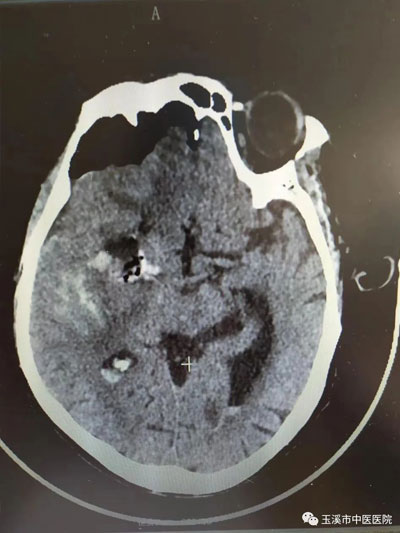

手術(shù)前顱腦CT提示:右側(cè)島葉、右側(cè)基底節(jié)區(qū)腦出血出血量估算大約50ML,部分血液破入側(cè)腦室。

手術(shù)后顱內(nèi)血腫基本清除。